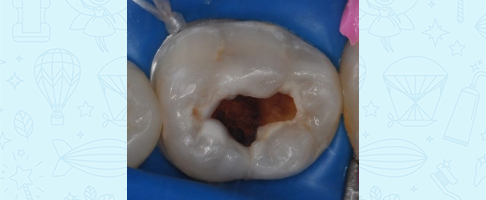

Лечение кариеса, восстановление зуба коронкой

Лечение кариеса молочного зуба, восстановление коронкой и герметизация фиссур с применением закиси азота

Лечение кариеса и пульпита молочных зубов во сне, восстановление коронками

Лечение пульпита молочного зуба, восстановление коронкой

Лечение пульпита молочного зуба, восстановление коронкой

Лечение пульпита молочного зуба, восстановление коронкой